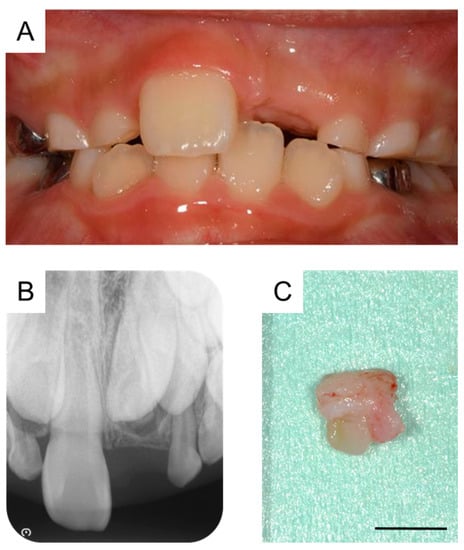

Orthodontic treatment was considered after the extraction of the third supernumerary tooth; however, the patient was uncooperative because of his intellectual disability. At 8 years and 9 months of age, a periapical radiograph revealed no change in the location of the permanent maxillary left central incisor (Figure 5A,B). Thus, under physical restraint and local anesthesia, the gingiva was surgically removed using an electrocautery device to expose the surface of the crown (Figure 5C).

Following surgical exposure, the incisor gradually erupted in the oral cavity (Figure 6). At 9 years and 7 months of age, as confirmed by radiographic examination, no new supernumerary tooth had reoccurred. Intraoral examination revealed mesial inclination of the permanent maxillary left central incisor and a space shortage for the maxillary incisors (Figure 7). The patient is gradually showing an improvement in readiness for dental treatment. Therefore, long-term follow-up will be performed, and orthodontic treatment will be considered according to the wishes of the patient and parents.

Figure 5. Fenestration of the maxillary left central incisor. (A) Intraoral photograph and (B) periapical radiograph after the extraction of the third supernumerary tooth at the age of 8 years and 9 months. (C) Intraoral image just after fenestration of the maxillary left central incisor at the age of 8 years and 9 months.